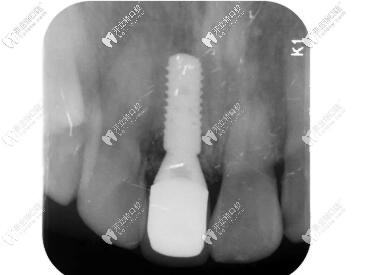

術(shù)后CBCT顯示植入正確的三維位置,種植體唇側(cè)骨量充足;

瑞士iti鈦親水BL 4.1mm*10mm種植體

X線片顯示就位良好;

瑞士iti親水BL種植體種植后x片